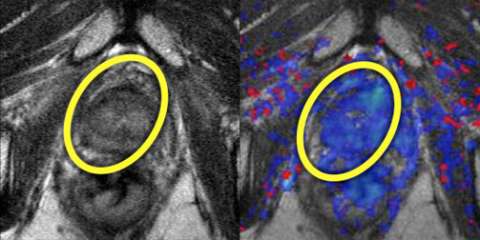

Imaging

LEFT: T2-weighted image after treatment shows normalization of T2 signal with reappearance of the normal peripheral-transitional zone border.

RIGHT: Color perfusion map shows correspondingly decreased perfusion (blue pixels) consistent with response to treatment.